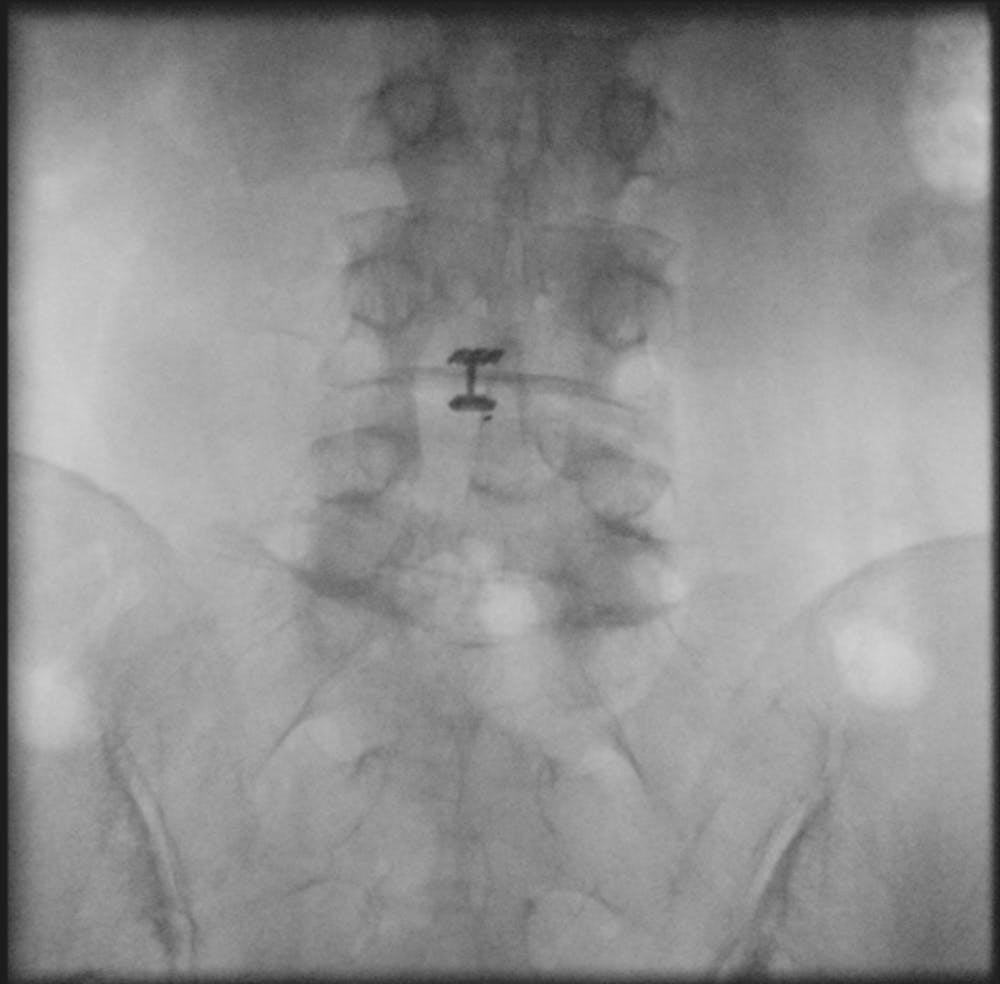

The Barricaid anular closure device is implanted after a microdiscectomy (a procedure to resolve the pain and discomfort associated with a lumbar herniated disc). The device anchored to the adjacent vertebrae, in a minimally-invasive spine surgery, performed on an outpatient basis by Dr. Jonathan Stieber.

Intrinsic Therapeutics developed the Barricaid device to close large defects in the annulus, the outer part of a spinal disc.

- Barricaid is used after discectomy, which is a surgery to remove lumbar herniated disc material that may be pressing on a nerve root or the spinal cord, causing pain.